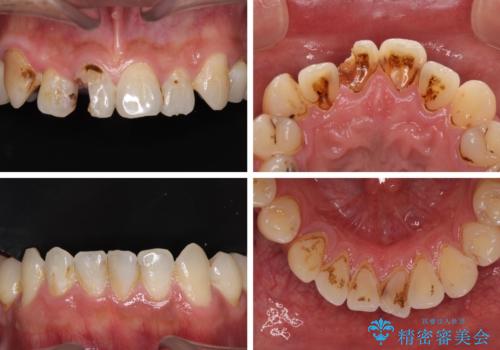

- 前歯や奥歯の虫歯を放置しており、それらの治療を契機に真っ白な歯にしたいとのことで来院された患者様です。

咬み合わせを改善するに当たって、抜歯しなければならない歯や歯列の改善が必要な箇所があったため、矯正治療やインプラント治療から始めていくこととしました。

不自然なくらい真っ白にしたいとのことでしたので、透明感のないフルジルコニアクラウンを用いて補綴することとしました。